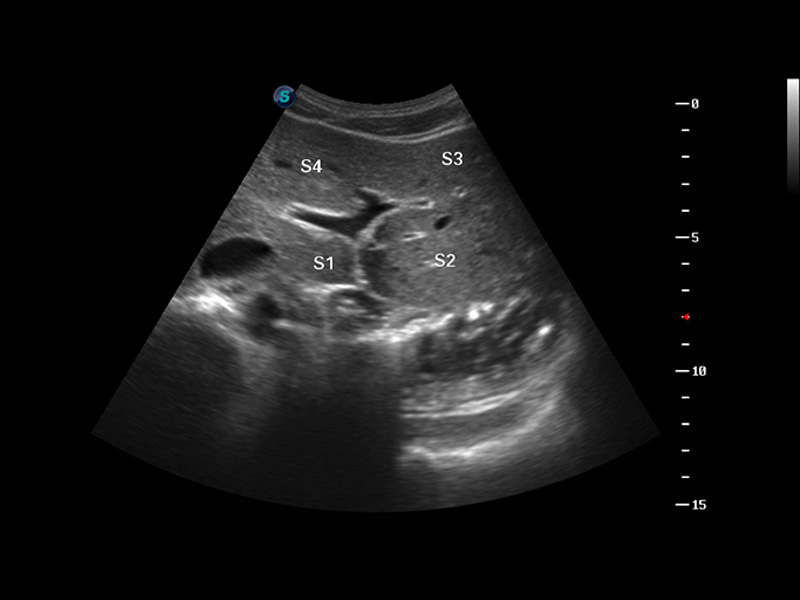

S8 EXP便携式彩色多普勒超声诊断仪是球速体育入口研发的高端全身应用型便携彩超。高通道的VIS平台融合可视化(Visual)、智能化(Intelligent)和人性化(Smart)的特点,配以球速体育入口自主研发生产的探头大家族,使您能够快速、准确的获得病人信息,提高工作效率的同时减轻疲劳。

μ-Scan微米成像

谐波成像

空间复合成像

3D/4D成像